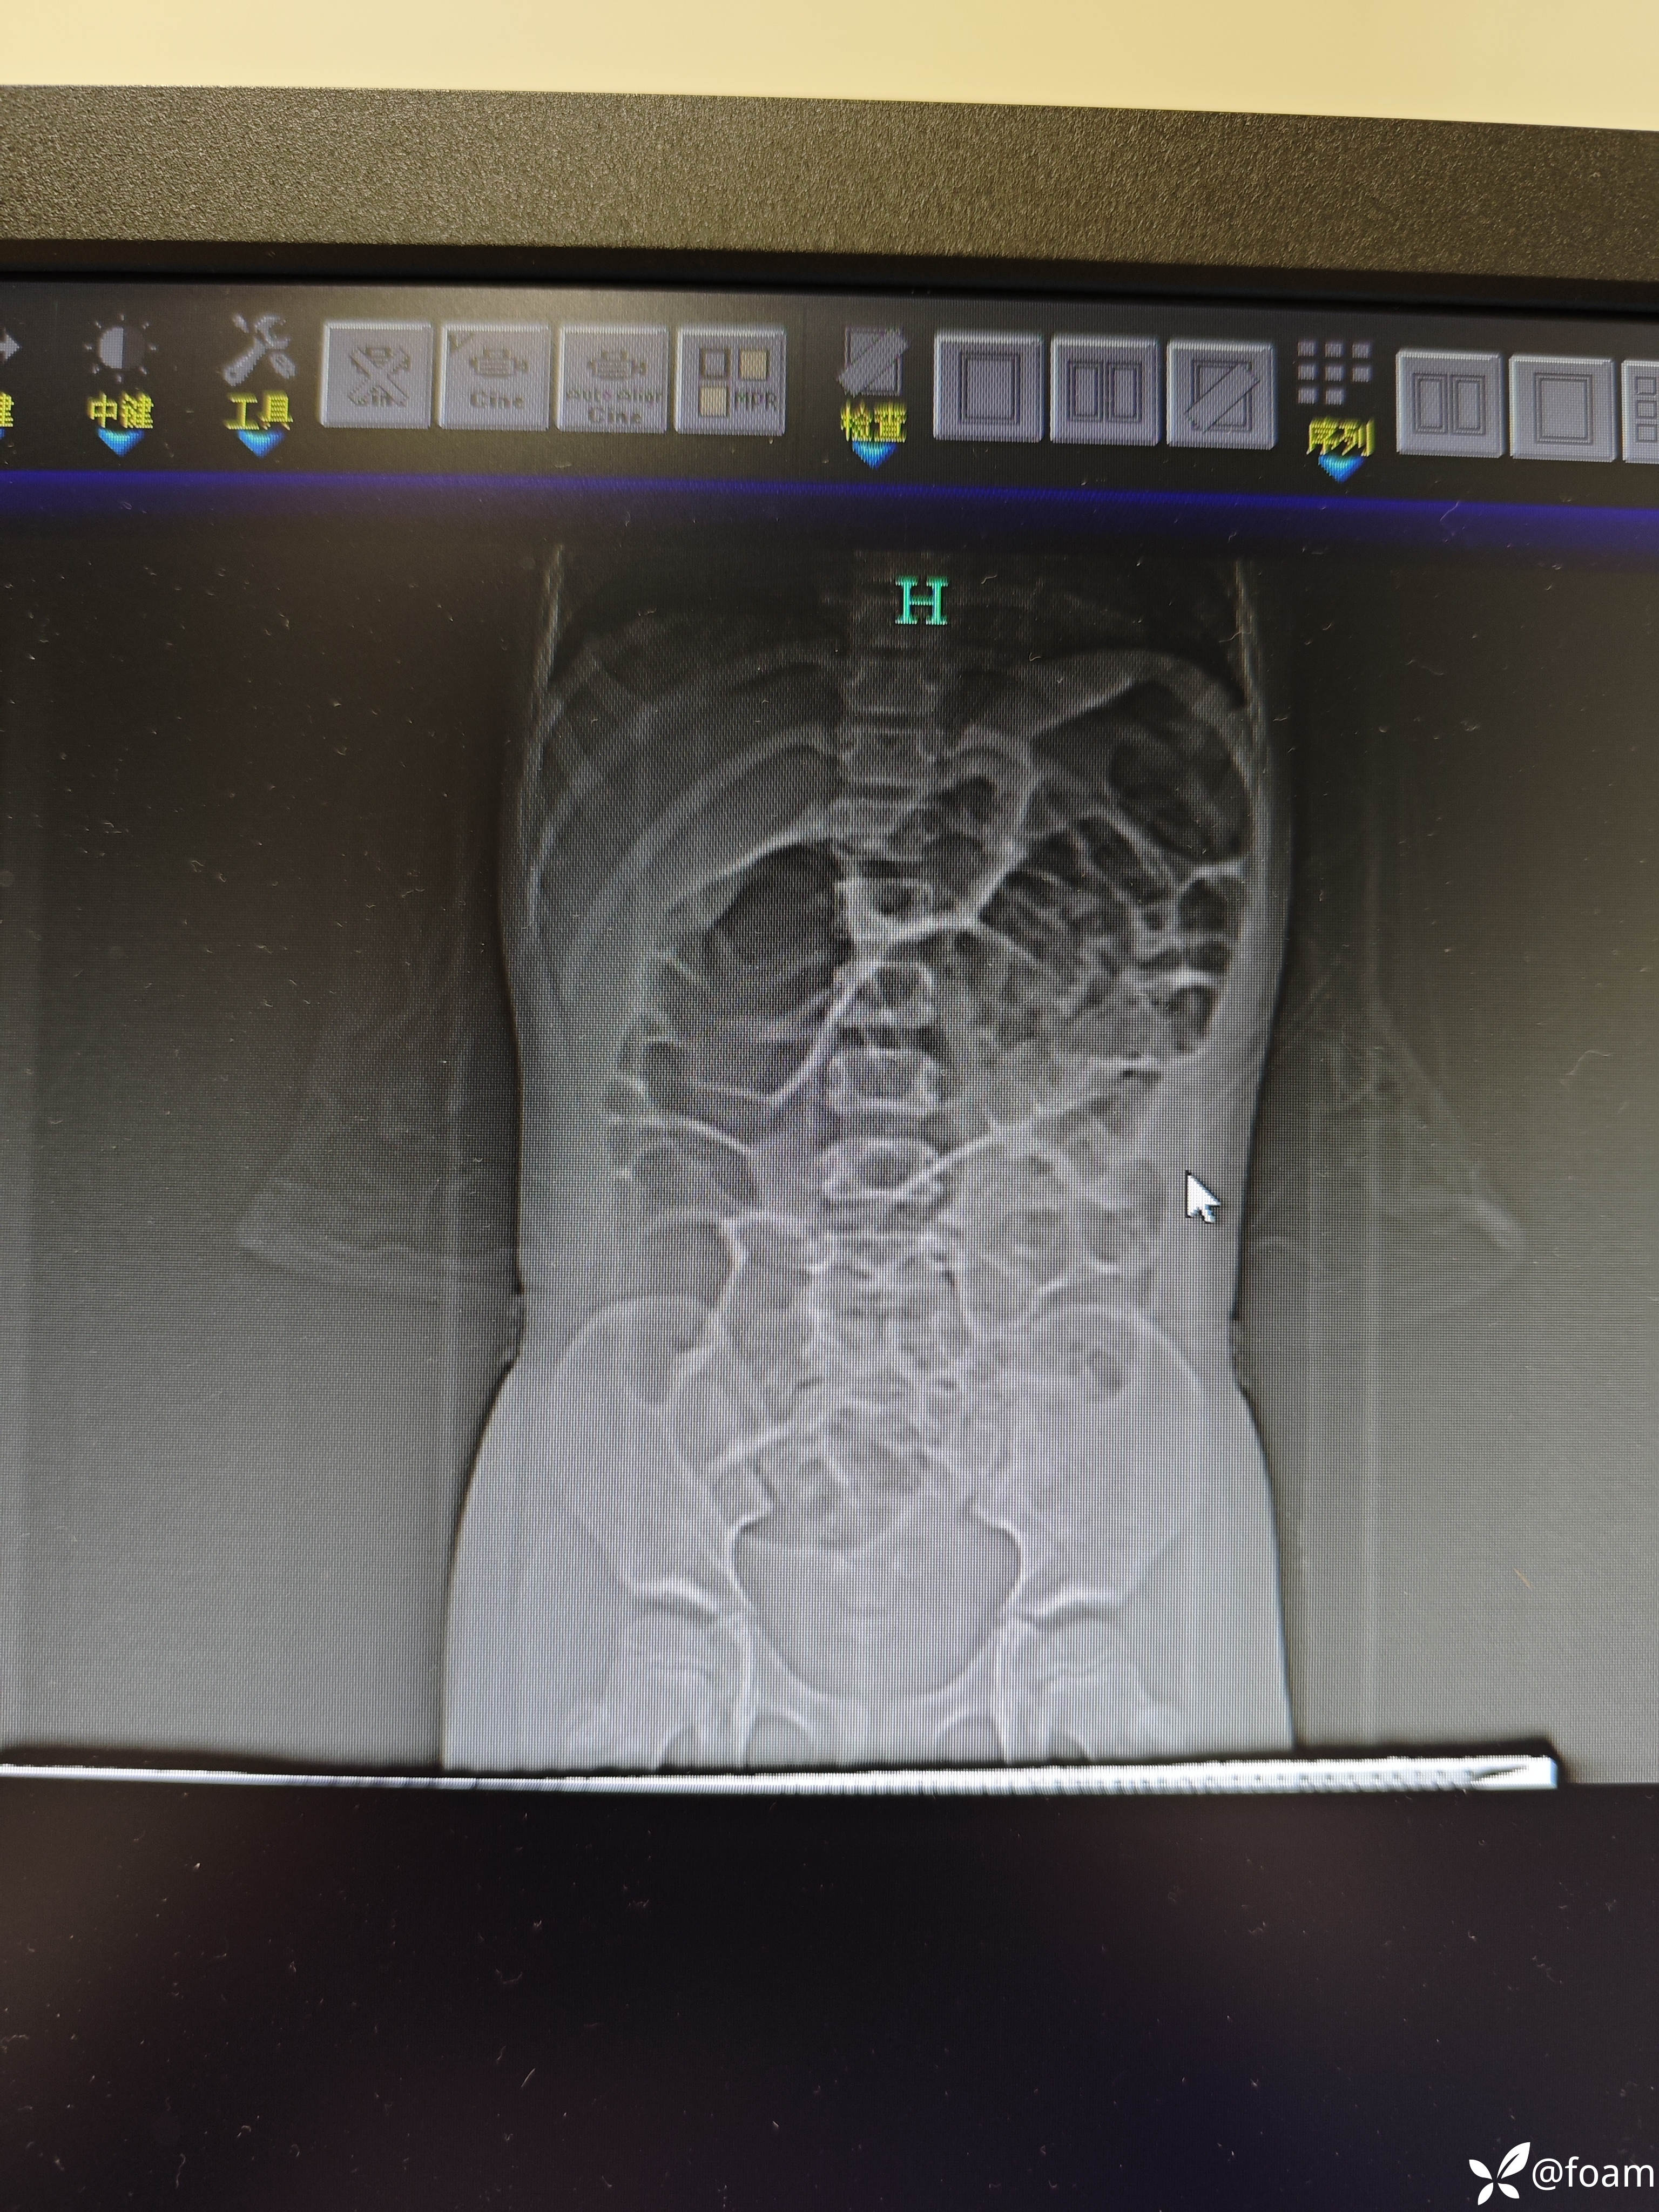

患儿4岁,3天前进食外卖(一起进食的孩子有多人发病,表现腹痛呕吐腹泻)后出现腹痛呕吐,无发热,大便未解。一天前腹痛加重,呕吐一天2-3次。纳差,精神欠佳。查体 生命体征稳定,痛苦貌,全腹稍紧张,两下腹压痛明显。

腹部CT不会看,请老师们看看,临床考虑什么,治疗方案。